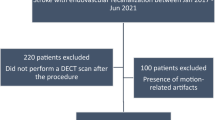

In this retrospective cohort study, 39 patients (21 males, 18 females, mean age 69 ± 11 years, range 45–90 years) with a TwinSpiral DECT scan as follow-up after EVT in patients with acute ischemic stroke were included. Scans were performed between November 2019 and July 2020. Patients were identified through the institutional radiology information system with the search terms “dual-energy” and “mechanical thrombectomy” in the radiology reports. Inclusion criteria were the availability of TwinSpiral DECT images within 24 h after EVT and at least one additional follow-up examination within 48–72 h after the TwinSpiral CT scan, either done by a CT with a non-contrast phase, or a magnetic resonance imaging (MRI) with a susceptibility weighted imaging (SWI).